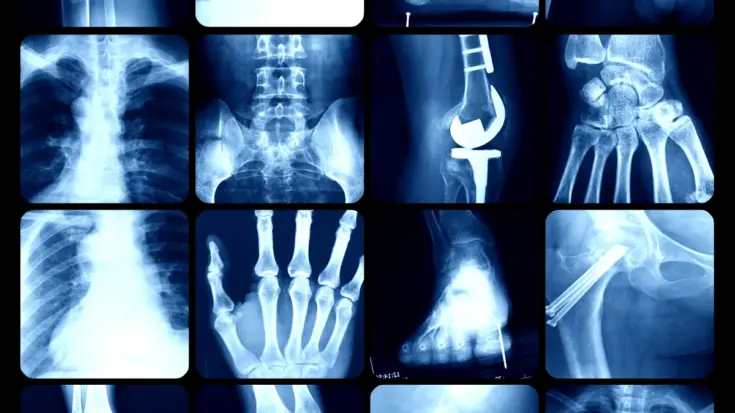

From the many benefits provided by X-ray detectors, this tool is used by many sectors, one of which is the medical industry. X-ray detector for medical industry are used to capture and measure X-ray radiation passing through the patient’s body to produce images.

X-ray detector for medical industry is used to capture and measure X-ray radiation passing through the patient’s body to produce images.

This device can visualize the internal body without the need for surgery, thus greatly assisting doctors in diagnosing and planning treatment.

In the medical world, this detector is applied in various needs for radiography, fluoroscopy, and CT scans.